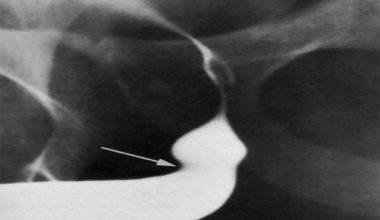

Üretra darlığı erişkin erkeklerde yaygın olarak görülen bir durumdur. İdrar kesesinin dışarı ile olan bağlantısını sağlayan ve idrar yollarının son bölümü olan üretrada, herhangi bir nedenden dolayı daralma meydana gelebilir. Bu durumda kanalın genişliği azalacağı için, içinden idrar geçmekte zorlanır. Hatta meni akışı da yavaşlayabilir.

Üretral darlığının tedavisinde en sık kullanılan tedavi yöntemleri internal üretrotomi ve üretroplasti ameliyatıdır.

Dilatasyon, genişletme anlamına gelir. Üretral dilatasyon, üretranın genişletilmesi demektir. Ameliyat sonrası, darlık bölgesinde yeniden daralma olmaması için metal ya da plastik bir madde sokularak uygulanır. Ancak üretral dilatasyon işleminin etkisinin olup olmadığı tartışmalıdır.

Dilatasyon işlemini hasta kendi kendine yapabileceği gibi, bu işlem doktor tarafından da yapılabilir. Dilatasyon işleminde idrar kanalı sert bir idrar sondası ya da buji adı verilen özel metaller ile genişletilir. Dilatasyon işlemi, poliklinik, hastane ya da evde gerçekleştirilebilir. Hastanın uyutulması gerekmez. Önce idrar kanalının içine uyuşturucu etkisi olan jel sıkılır. Daha sonra dilatasyon işlemi yapılır. Hasta dilatasyon işleminden hemen sonra günlük işlerine geri dönebilir.